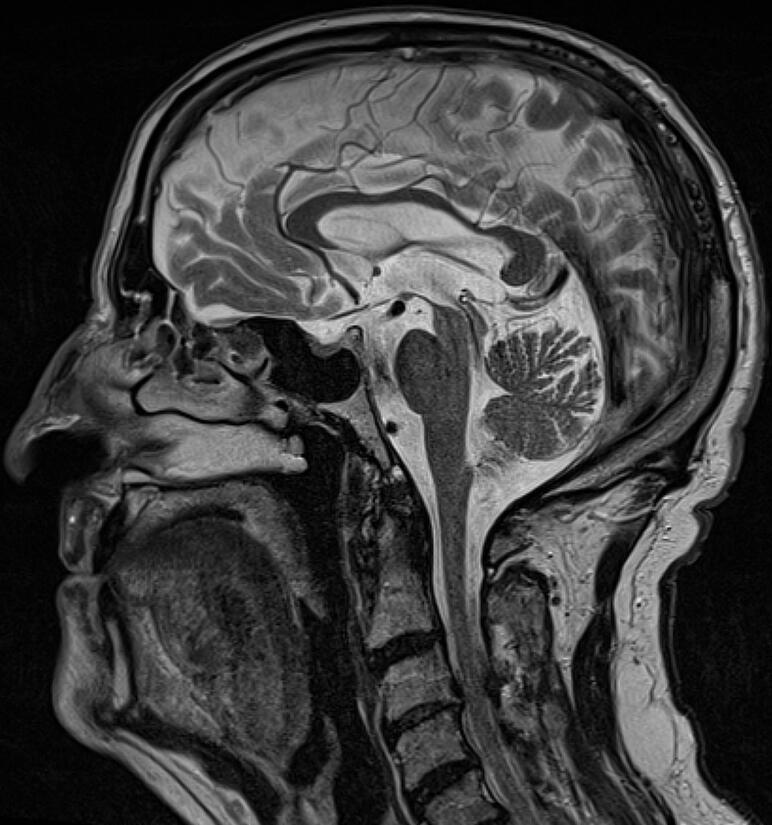

Progressive supranuclear palsy (MRI)